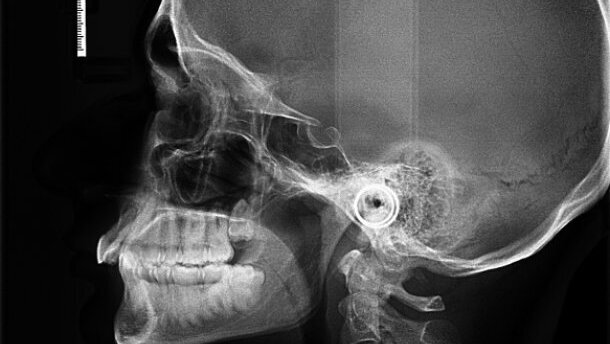

Keeping the patient’s professional commitments and the limitation of aligner therapy in mind it was decided to place a fixed bonded appliance for a short duration, along with TADs placed between the maxillary central and lateral incisors bilaterally for intrusion of anterior teeth (Figs. 2a–d). Force systems to achieve intrusion of the incisors to be in force from day 1 for a duration of 3–4 months (Figs. 3a–d) and subsequently to shift him to K Clear for residual bite opening, space closure and final finishing. Attachments on the maxillary first molar and premolars, bilaterally were provided to provide better retention to the aligners. The K Clear aligners were placed for 5 months (Figs. 4a–d). At the end of active treatment, retainer was bonded from canine to canine in upper arch (Figs. 5a & b). Additionally, the patient was provided an Essix retainer for night time wear. The patient is in retention for the past 1 year and the occlusion as well as other movements achieved are stable (Figs. 6a–d).

This case was started with a pre-adjusted bonded appliance along with the use of TADs placed close to the teeth requiring intrusion. When used in this manner, the flexible NiTi wires cause alignment and the vertical forces generated lead to intrusion and flaring of the incisor teeth. Since TADs also cause trauma, a RAP phenomenon is generated, which causes an increase in the rate of tooth movement. The bite opening led to the increase in the upper incisor to NA from 12 degrees to 22 degrees (Figs. 7a & b). This led to minor spacing appearing between the anteriors. Clear aligners have been shown to provide good control where tipping movements are used[5] and such controlled movements led to a near ideal finish for this case. The K Clear appliance was selected in this case based upon the variable thickness used to achieve different movements in a predictable manner and our experience with it.